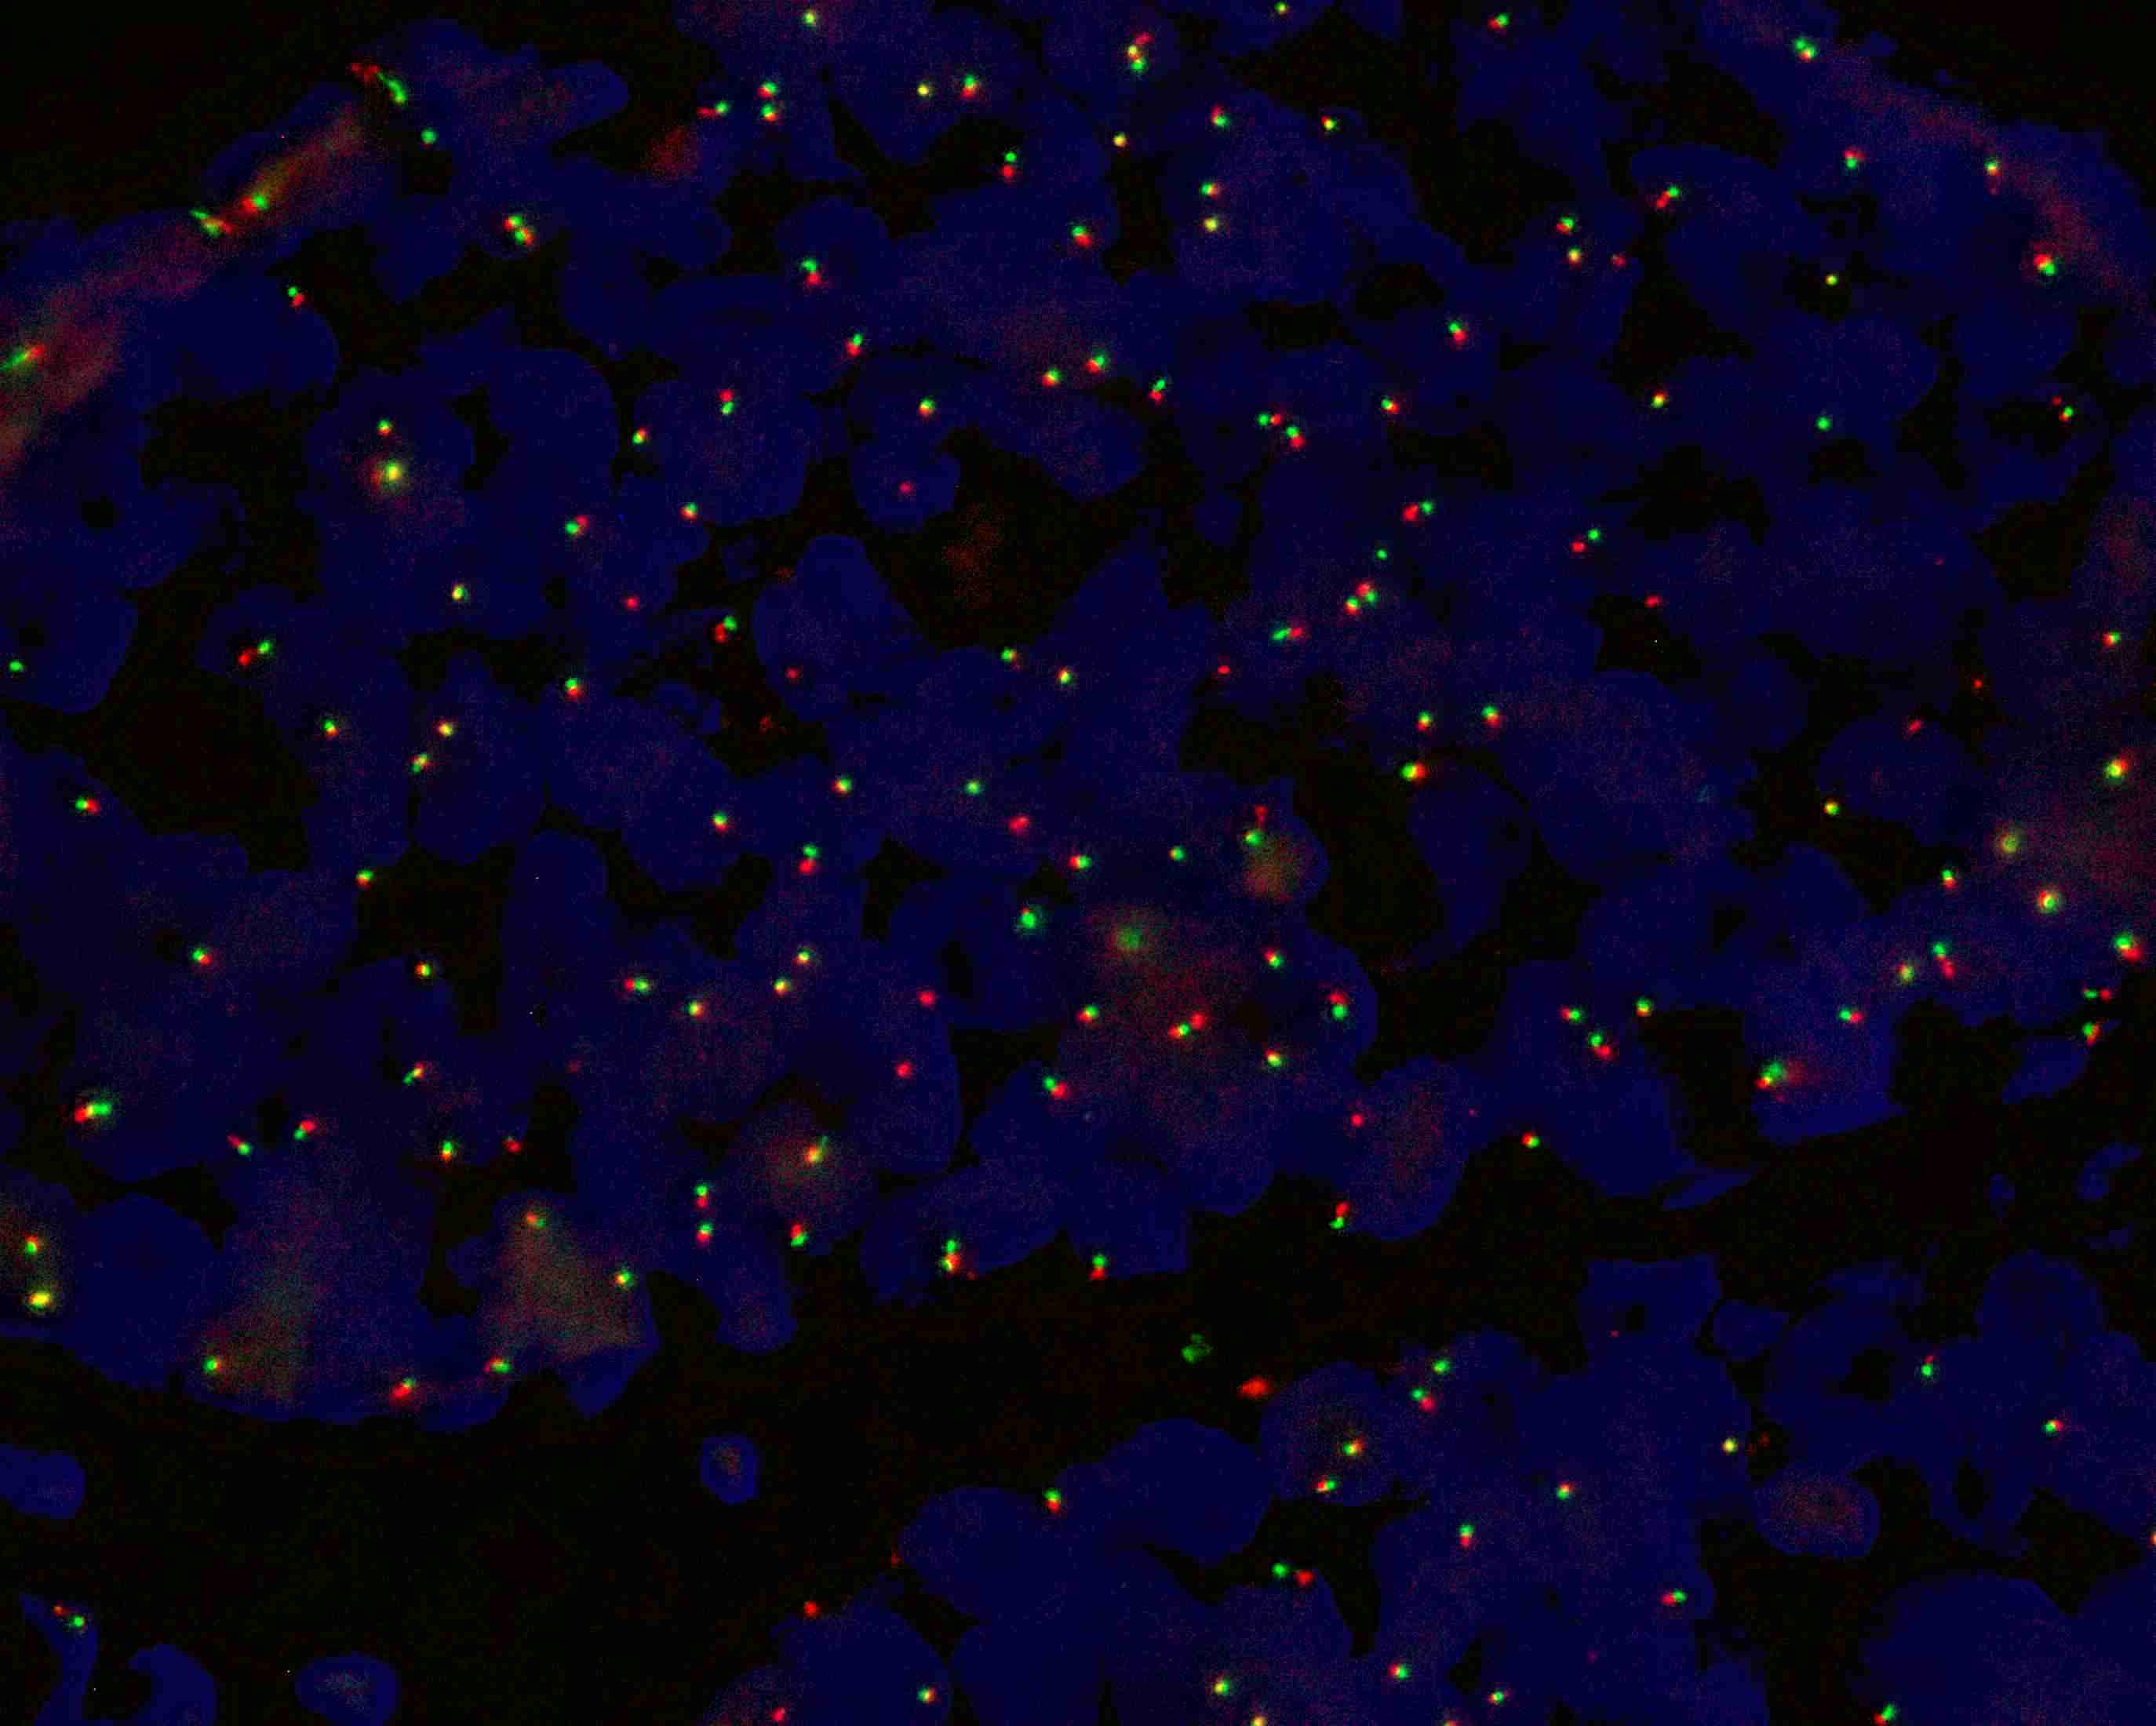

MYB gene break apart probe reagent

MYB gene 5’ end labeled as orange, with a length of 487 kb; MYB gene 3’ end labeled as green, with a length of 777 kb.